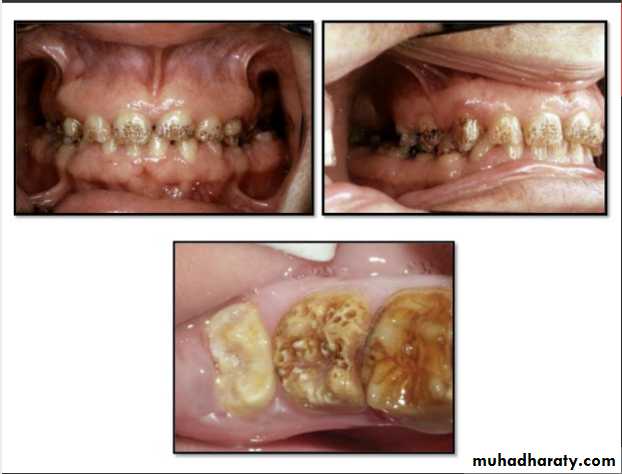

Hypoplastic Amelogenesis Imperfecta:

* Due to some defect in ameloblasts enamel fails to develop to its normal thickness dentin exposed the tooth shows yellowish-brown color.*Enamel is randomly:

pitted .

rough OR smooth &glossy.

*The occlusal surfaces of the posterior teeth are relatively

flat with low cusps due to attrition of cusp tips that were initially low and not fully formed. An anterior open bite may be noted..

Generalized hypoplastic type

Amelogenesis ImperfectaAffects primary &permenant dentition

Severe mottling of the enamel surface.

Hypomaturation Amelogenesis Imperfecta:

*Enamel is normal in form on eruption but:

opaque.

white to brownish-yellow.

softer than normal.

tends to chip from underlying dentin.

Hypocalcified Amelogenesis Imperfecta:

*Enamel matrix is formed in normal quantity,poorly calcified.

When newly erupted:Enamel is normal in thickness, normal form, but weak , and opaque or chalky in appearance.

With years of function:

Coronal enamel is removed except for cervical portion that is occasionally calcified better.